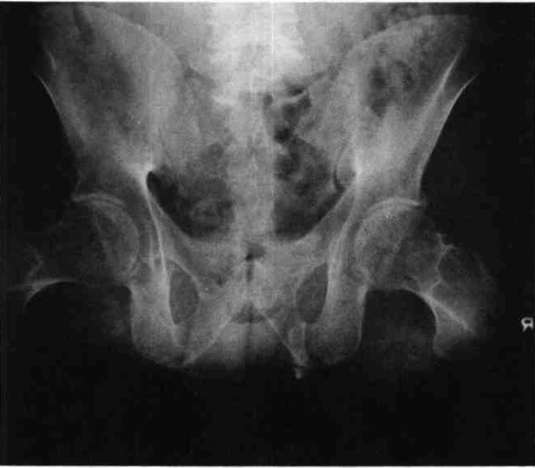

The patient, a 37-year-old white male, received traumatic injuries while involved in an auto accident in October 1965. Both limbs were severely crushed, and very high amputations were necessary. The physical appearance of the patient resembled that of a bilateral hip disarticulation amputee; however, closer examination and X-rays of the patient revealed that femoral neck and head were present bilaterally. The remaining skeletal structures of the femurs are approximately 3" on the left and 4" on the right side (Fig. 1).

Figure 1: